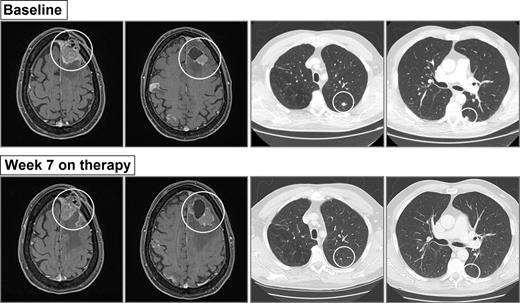

Six patients achieved extracranial objective response in the presence of persistently detectable ctDNA (i.e., ctDNA positive at baseline and on-therapy). Four of these patients had >10-fold decrease in their ctDNA on-therapy compared with baseline, and another patient had a >5-fold decrease in ctDNA (Fig. 1). The remaining patient (SCC11-0270) had persistent, albeit low levels of ctDNA (baseline: 5, week 6: 4, and week 12: 5 copies/mL plasma), showed the lowest extracranial disease volume at baseline (SPD = 178 mm2), and achieved a complete response (CR) extracranially. Interestingly, this patient also had the highest intracranial disease volume at baseline (SPD = 1,487 mm2) and had significant intracranial progression on first restaging CT imaging at 7 weeks, suggesting that the detectable ctDNA may be derived from the high-volume intracranial metastases (Fig. 3).

This patient with melanoma had significantly larger volume of disease in the brain than extracranially (SCC11-0270). Patient received single-agent nivolumab, and the restaging scan after 7 weeks confirmed disease progression in the brain and CR in the lung (only site of extracranial disease). Metastases on CT and magnetic resonance images are circled in white.

There are several possible reasons for the failure of ctDNA to reflect intracranial disease activity accurately. First, ctDNA has been shown to reflect tumor burden (18), and the low tumor burden in the brain may result in lower levels of available ctDNA. In 1 patient, persistent ctDNA positivity appeared to reflect the large, and unresponsive intracranial metastases, rather than the low burden extracranial disease, which responded to immunotherapy. Although only a single case, this patient provides compelling evidence that brain disease volume is often too low for ctDNA detection.